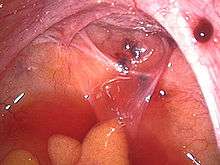

Laparoscopy

Laparoscopy, a surgical procedure where a camera is used to look inside the abdominal cavity, is the only way to officially diagnose endometriosis as it permits lesion visualization, unless the lesion is visible externally, e.g. an endometriotic nodule in the vagina. If the growths are not visible, a biopsy may be taken to determine the diagnosis.[50] Surgery for diagnoses also allows for surgical treatment of endometriosis at the same time.

To the eye, lesions can appear dark blue, powder-burn black, red, white, yellow, brown or non-pigmented. Lesions vary in size. Some within the pelvis walls may not be visible, as normal-appearing peritoneum of infertile women reveals endometriosis on biopsy in 6–13% of cases.[51] Early endometriosis typically occurs on the surfaces of organs in the pelvic and intra-abdominal areas. Health care providers may call areas of endometriosis by different names, such as implants, lesions, or nodules. Larger lesions may be seen within the ovaries as endometriomas or "chocolate cysts", "chocolate" because they contain a thick brownish fluid, mostly old blood.

Frequently during diagnostic laparoscopy, no lesions are found in women with chronic pelvic pain, a symptom common to other disorders including adenomyosis, pelvic adhesions, pelvic inflammatory disease, congenital anomalies of the reproductive tract, and ovarian or tubal masses.[52]